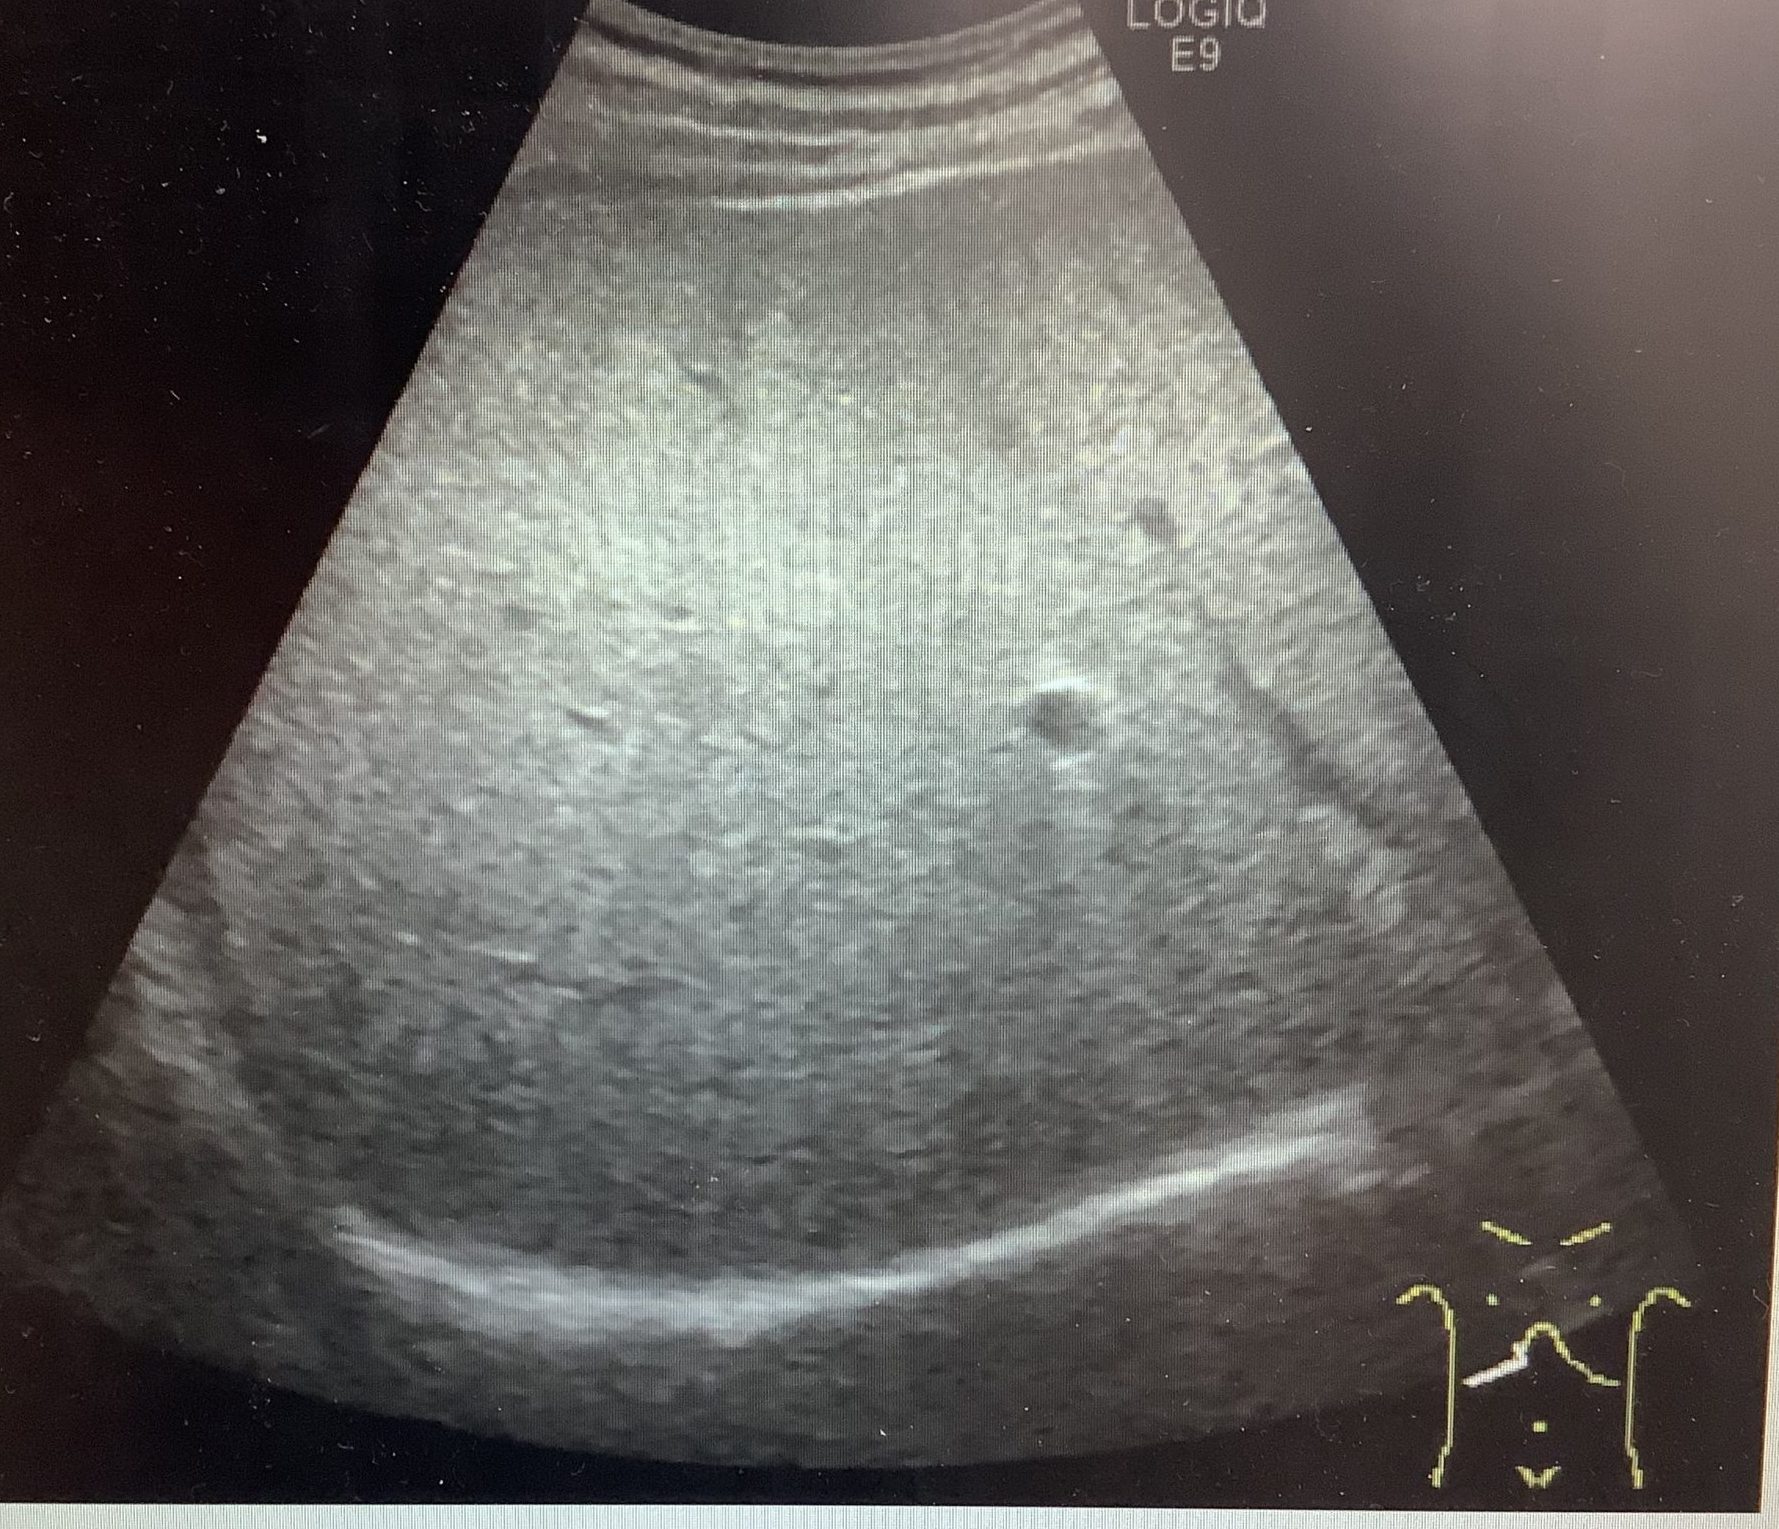

こんにちは、四日市消化器病センター検査の杉本です。

今回は脂肪肝についてお話しします。

人間ドックで腹部エコーを受けていただいた方で、所見に脂肪肝とかえってきた方はいらっしゃいませんか?

脂肪肝とは、肝臓の10%以上に中性脂肪が沈着した状態をいいます。

脂肪肝の原因は、アルコールによるものと、アルコールによらないものがあります。

アルコールによらないものは、ほとんどが肥満によるもので、お酒を飲まない人でも

肝臓の障害が継続して、肝硬変、肝癌へと進行してしまう人がいることがわかってきました。

非アルコール性脂肪性肝炎はメタボリックシンドロームの予防が最も基本的な治療法でもあり、

予防法なのです。

脂肪肝と言われた方は一度かかりつけの先生に相談されることをおすすめします!